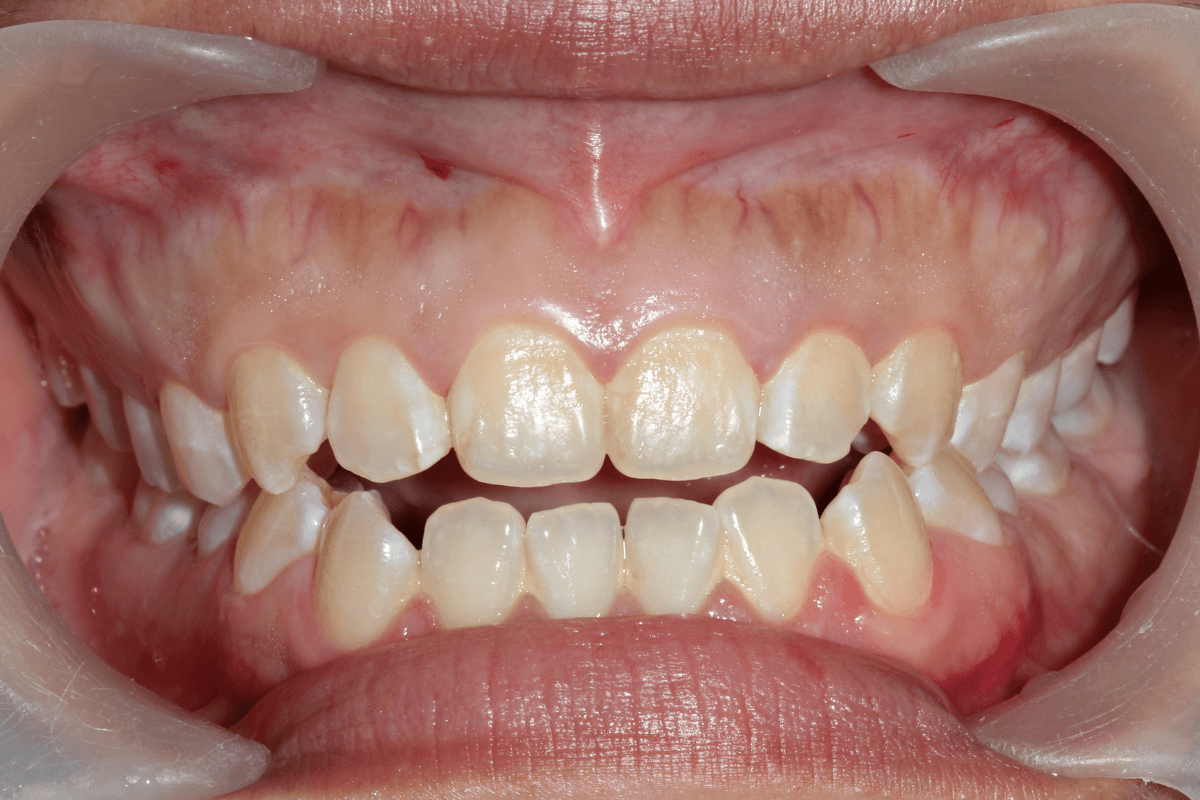

Съдържание Кръстосана захапка – Какво представлява? Кръстосаната захапка е една от най-често срещаните форми на малоклузия (неправилно подреждане на зъбите), при която горни зъби захапват вътре спрямо долните, вместо да ги покриват отвън, както е при нормална оклузия. Тази зъбна аномалия може да засегне единичен зъб или група зъби, засягайки предната или задната част на […]